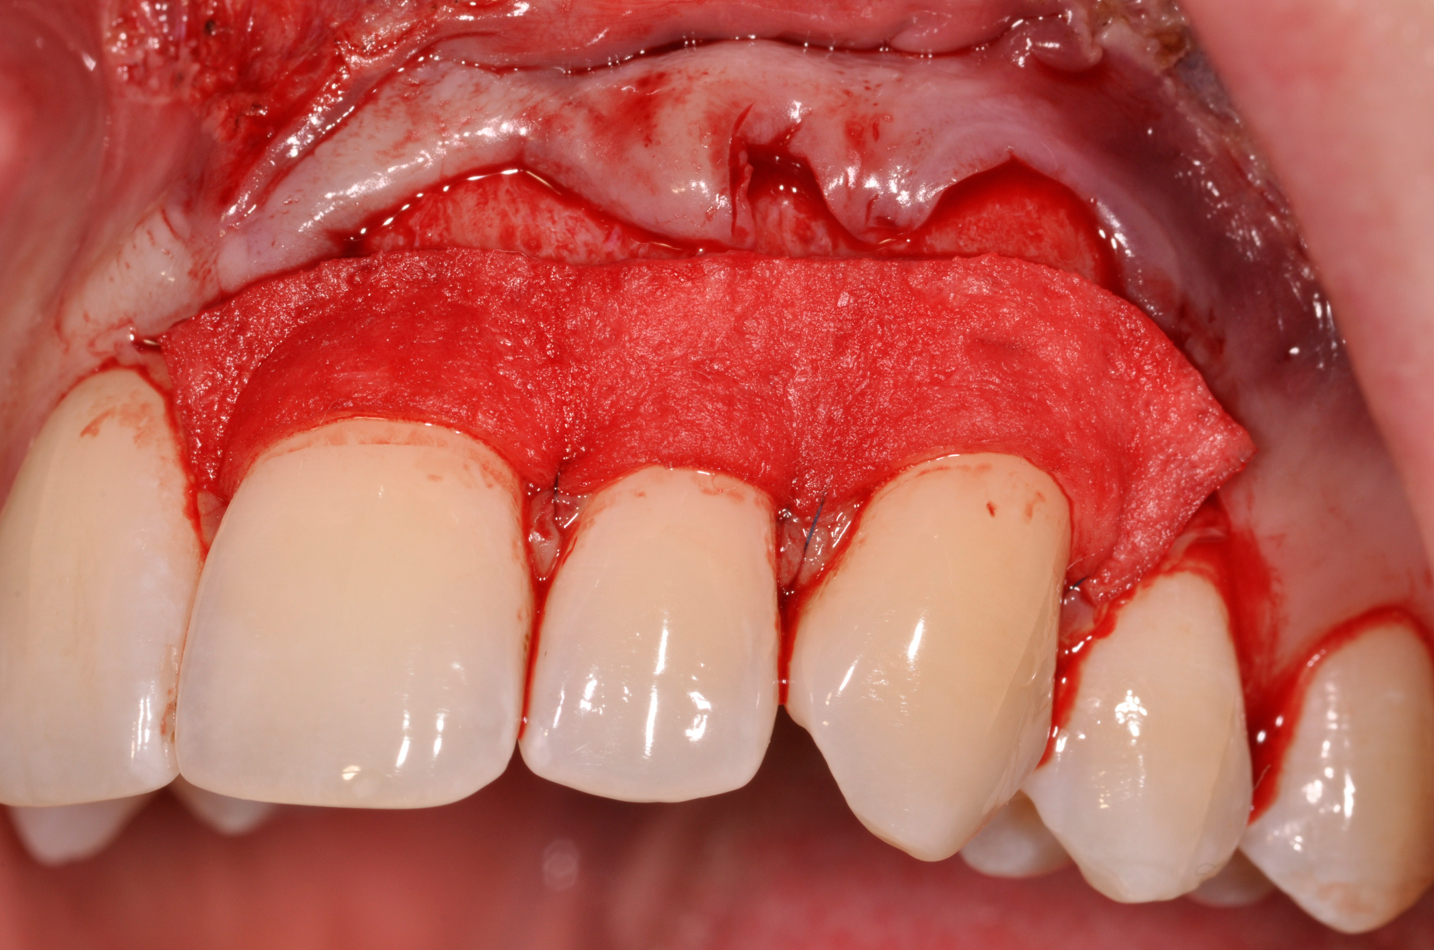

The flap approach follows an incision design where the crest of the papilla is preserved and a V-type incision is made in the papillary tissues (Figure 4). This allows the preexisting papillary tissues in the area just inferior to the contact point of the natural teeth affected to be used as a tissue bed to provide vascularization to the flap/dermis complex. Prior to securing the dermal matrix tissue, the papillary tissues that remain after the incision technique outlined must be de-keratinized by using a #4 round diamond bur. This allows for the introduction of initial blood flow and vascularization of the dermal matrix tissues and nourishment of the coronally repositioned flap in the critical area of the interproximal papillary tissues. After securing the dermal matrix tissue from the palatal/lingual aspect of the teeth being treated and coronally repositioning the buccal flap, closure is achieved using an interrupted sling suturing technique.

Fig 4. V-type incision to preserve the crestal portion of the papilla.

Figure 4